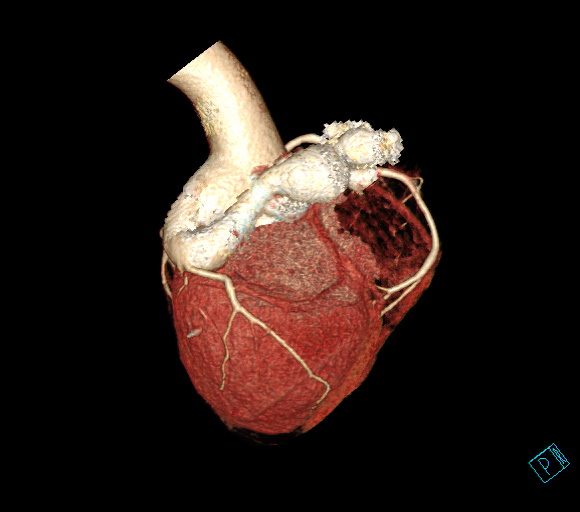

图:患者术前

受术患者是一名31岁的小伙子,活动后出现胸闷不适,发作时伴有气促、恶心不适,安静休息后症状缓解,活动后症状再次出现,患者未予重视,未就医治疗,期间症状仍反复发作,严重影响日常生活。在亲戚的介绍下,他慕名来到我院心血管内科就诊,心血管内科主治医师朱建峰接诊后为患者行冠状动脉造影术,检查提示巨大左冠状动脉右房瘘,瘘道最窄处约10cm,心脏超声提示左心室增大。